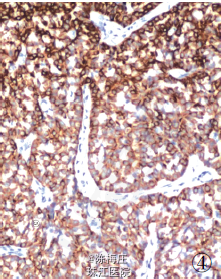

最后诊断:右乳神经内分泌癌;结肠腺癌;左侧卵巢Brenner 瘤。 遂行右乳肿物切除术+ 乙状结肠癌切除术及左侧附件切除术。术中所见:右乳肿物分叶状,与周围界清;乙状结肠肿物与周围无粘连;左侧卵巢肿物包膜完整,未见腹水。术后病理显示右乳腺内分泌癌,乙状结肠腺癌,左侧卵巢Brenner 瘤。